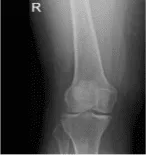

Opinión AP